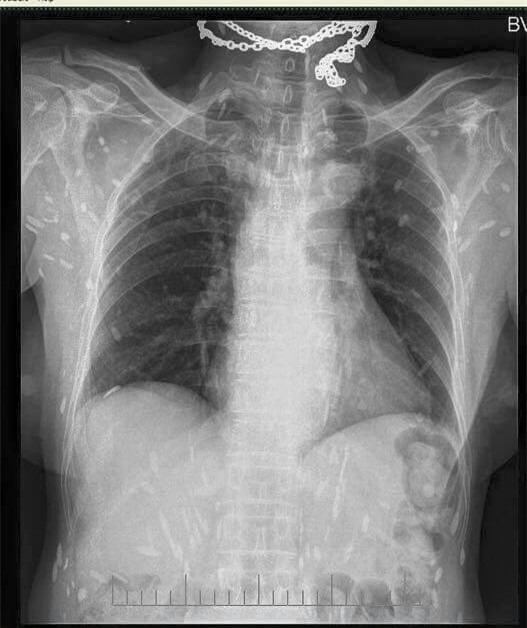

Mấy ngày nay trên mạng chia sẻ hình ảnh phim chụp Xquang của một bệnh nhân bị sán dải lợn, ấu trùng sán lợn di chuyển khắp cơ thể.

Hình ảnh đang lan truyền trên mạng xã hội được cho là của bệnh nhân đã khám và điều trị tại Bệnh viện Đa khoa trung ương Thái Nguyên. Bức ảnh được rất nhiều người chia sẻ kèm theo lời cảnh báo từ nay nên nói không với các loại thịt tái, sống, rau sống, tiết canh.

Hơn 30 năm gắn bó với chuyên ngành ký sinh trùng, bác sĩ Đề cho rằng hình ảnh này rất phổ biến, may mà ấu trùng sán lợn chưa lên não.

Bác sĩ Đề cho biết có bệnh nhân ông gặp có 300 ấu trùng sán lợn ở não và 300 ấu trùng sán lợn ẩn dưới da. Các loại ấu trùng này chụp Xquang có thể nhìn được hết.

(Ảnh: fb BS Luong Quoc Chinh)